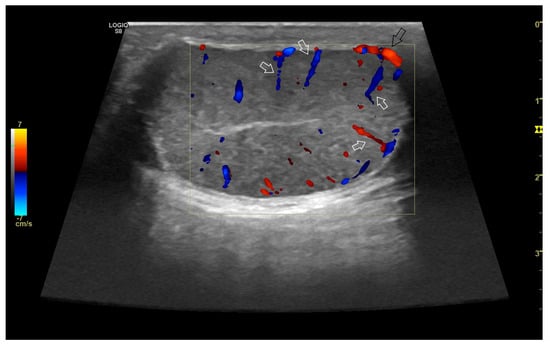

4. Colour Doppler and Power Doppler

4.2. Normal Findings

- Bigliardi, E.; Denti, L.; De Cesaris, V.; Bertocchi, M.; Di Ianni, F.; Parmigiani, E.; Bresciani, C.; Cantoni, A.M. Colour Doppler Ultrasound Imaging of Blood Flows Variations in Neoplastic and Non-Neoplastic Testicular Lesions in Dogs. Reprod. Dom. Anim. 2019, 54, 63–71. [Google Scholar] [CrossRef]